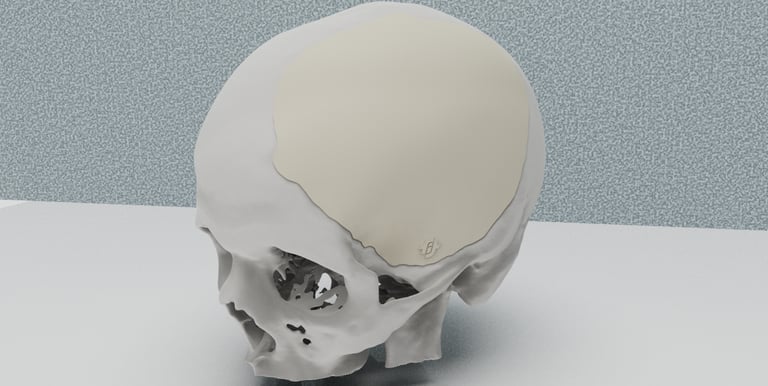

Craneoplastías en PMMA

Líderes en la fabricación de craneoplastías en Polimetilmetacrilato: tiempos récord de fabricación a partir de la tomografía con el defecto óseo. Diseñamos, fabricamos y esterilizamos.